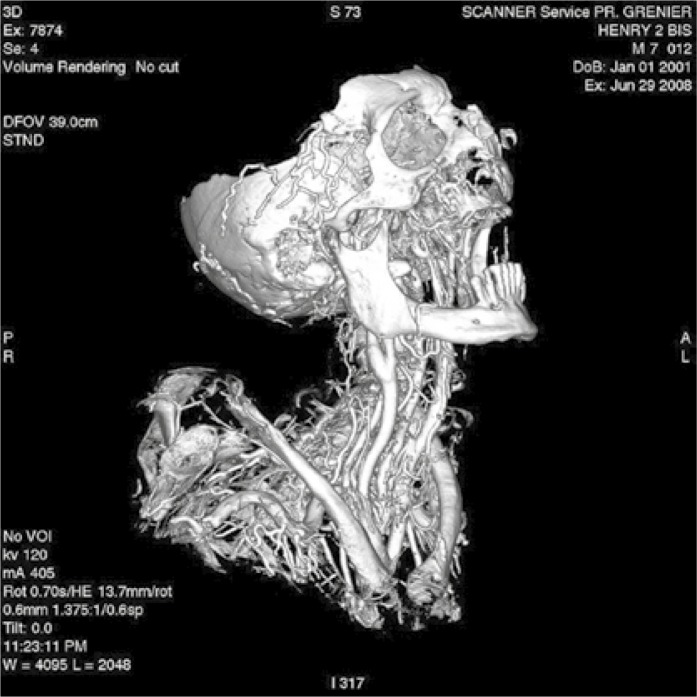

Preserved remnants of a 13th century autopsy…

And a CT scan of the same:

Wade and Nelson, Radiological evaluation of the evisceration tradition in ancient Egyptian mummies, 2013. These CT scans were performed on the mummy Djedmaatesankh, an ordinary woman from Thebes who died almost 3000 years ago. The body was eviscerated and filled with packages which possibly contained organs. A scarab and falcon were placed on the abdomen external to the body cavity.